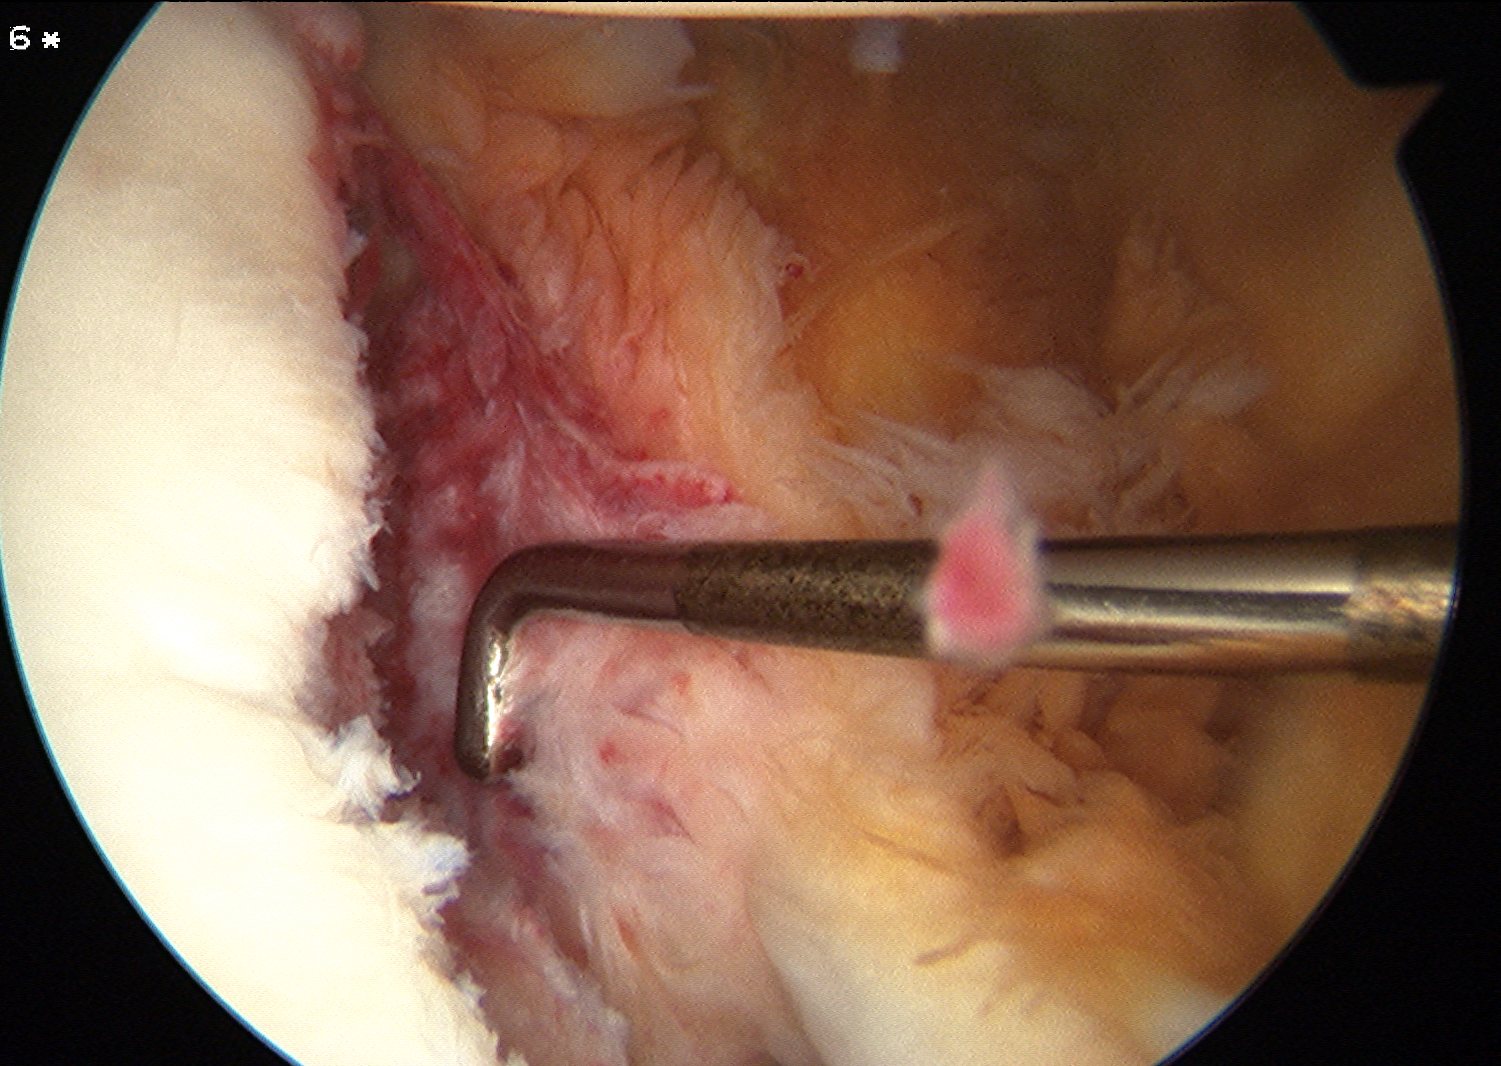

Mobilize labrum

Shoulder Scope Bankart RaspShoulder Stabilisation Labral Mobilisation

Labral mobiliser / rasp

- labral tear can be obvious, but may have partially healed or healed medially

- change camera to anterosuperior portal for better view

- mobilize until can see subscapularis muscle underneath

- need to be able to advance labrum medially and superiorly for repair